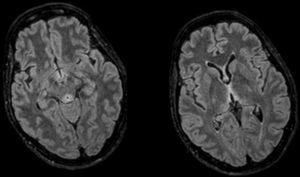

Upon arrival the patient scored 8–12 points in the GCS. Her only physical focality was the inexistence of oculocephalic reflexes. Given the patient's clinical manifestations, chronopathology, and negative tests, the initial suspicion included the possibility of WE and the patient was administered IV thiamine; 24–48h later the patient improved significantly and was bradypsychic, yet aware and collaborative. One cranial MRI was performed that confirmed the presence of thalamic, periaqueductal hyperintense, symmetrical lesions, mammillary bodies and quadrigeminal tubercles–all typical findings of WE and the patient was discharged early. Yet despite the patient's initial recovery, in the posterior follow-ups she showed sequelae noticeable in her gait and memory.

Diagnosis is clinical even though there are tests for assessment and support. The cerebral nuclear magnetic resonance is the modality of choice1,3 thanks to its specificity (93 per cent) and positive predictive value (89 per cent) being the CT scan discarded due to its low sensitivity. The typical lesions are symmetrical and they affect the medial thalamus, the mammillary bodies, the tectal plate, and the periaqueductal region8 (Fig. 1). The thiamine deficiency may be analysed using high resolution liquid chromatography or from the activity displayed by erythrocyte transketolase1,3,7 where it acts as a cofactor. In our patient we were unable to obtain any levels due to an extraction mistake that made our sample useless. The fast recovery after the administration is the best diagnosis as it occurred with our patient.